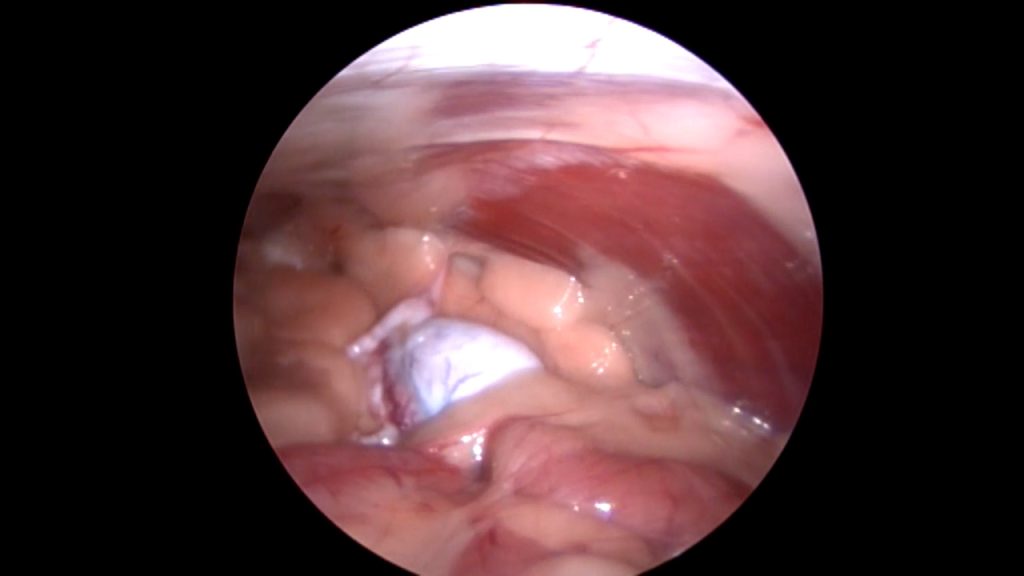

Denk hierbij bijvoorbeeld aan het verwijderen van een binnenbal die in de buik ligt (cryptorche testikel), waarbij er laparoscopisch geassisteerd wordt. Door middel van een echo is er eerst gekeken waar de testikel ligt.

Op de operatietafel kunnen we vervolgens met behulp van de scoop de cryptorche testikel nauwkeurig lokaliseren en bepalen waar de bloedvaten zitten, die we niet willen raken. Vervolgens kan dan zeer gericht een 2e trocar (dit is een canule van bijvoorbeeld 5 mm breed, waardoor je vervolgens met een tang de buik in kunt) geplaatst worden om de testikel tegen de buikwand te halen en te kunnen verwijderen. Al met al heb je dan 2 veel kleinere gaatjes in vergelijking met een echte buikoperatie.